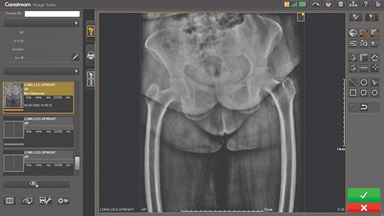

Our Carestream Focus HD 35/43 Retrofit Detectors, powered by Image Suite Software, are an ideal solution to step up to full digital X-ray for customers who simply cannot compromise on image quality. It seamlessly integrates into existing setups, bringing the power of full digital X-ray with minimal disruption and maximum clarity, along with the following benefits: